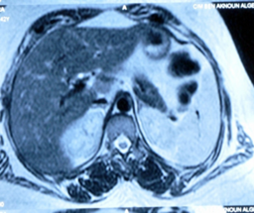

La tomodensitométrie abdominale avec opacification confirmait cette cholécystite avec un foie hétérogène, siège de multiples microlésions arrondies hypodenses, rehaussées légèrement après injection de produit de contraste (Figures 3, 4).

L’IRM abdominale objectivait des micronodules hépatiques iso-intenses T1-T2 évocateurs des séquelles tuberculeuse, sarcoïdose, autres.